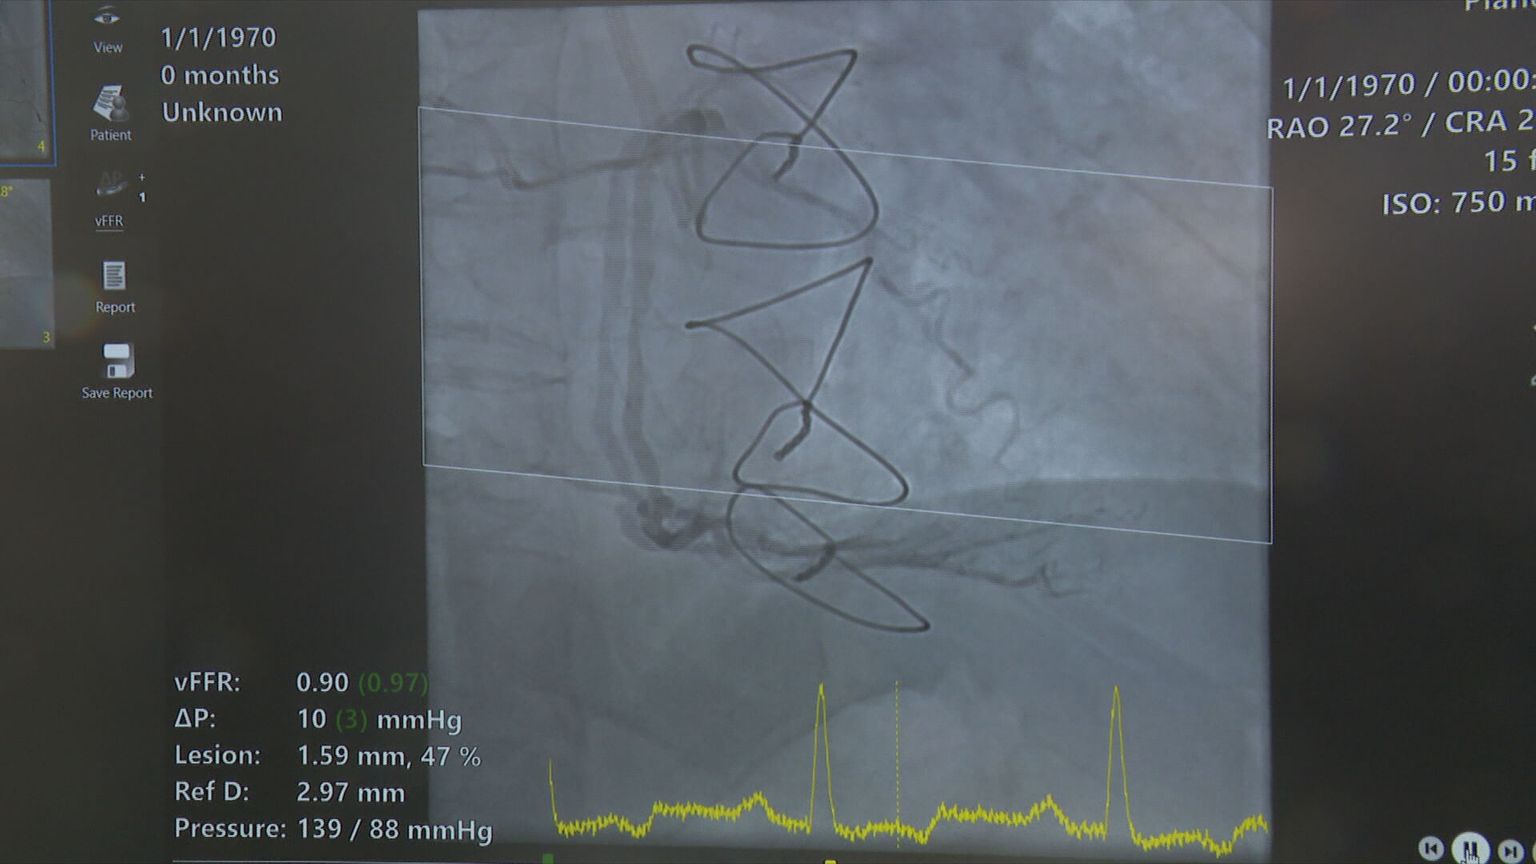

• Umjetna inteligencija u zdravstvu, ilustracija - 6 Foto: DNEVNIK.hr